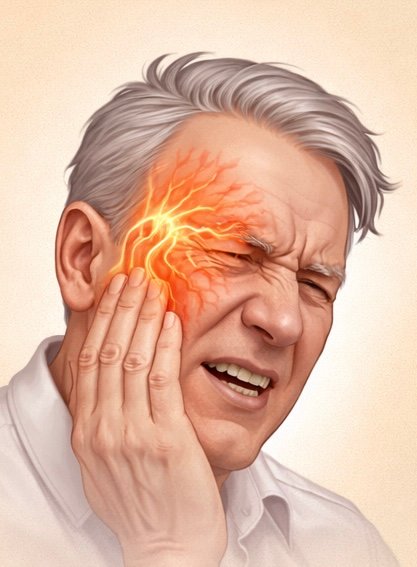

Trigeminal Neuralgia

Trigeminal neuralgia is a severe nerve pain condition affecting the face.

It causes sudden, electric-shock-like pain triggered by activities such as talking, chewing, or touching the face.Advanced treatments including nerve blocks and radiofrequency procedures can help control pain effectively.